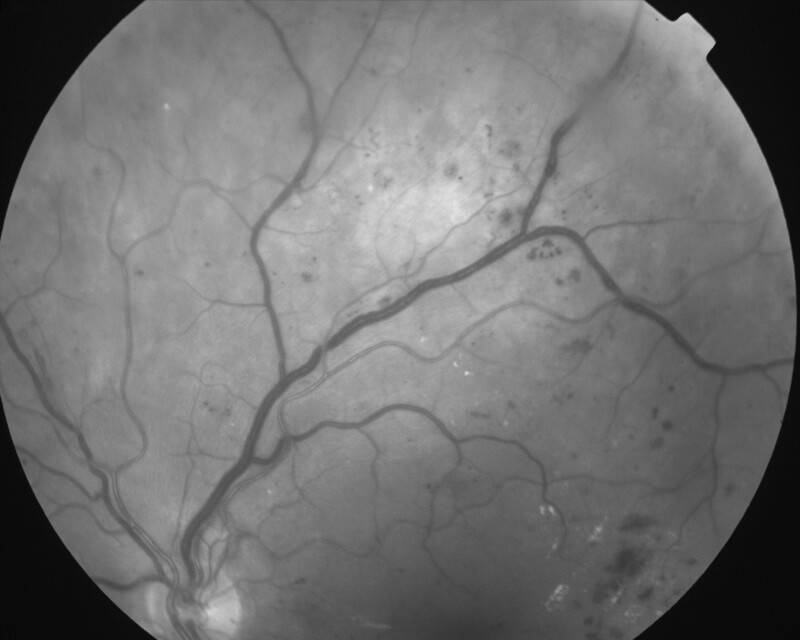

RETINOPATHIE DIABETIQUE PROLIFERANTE